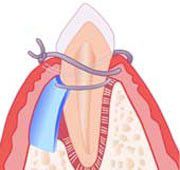

Placing synthetic bone

Placing synthetic bone

1. Bone Grafting

What is bone grafting?

The oldest technique used in regeneration surgery calls for placing various materials in the bone defect, to stimulate the patient's bone to re-grow.

Bone grafting has been used for over 75 years, but today's materials are much superior in stimulating new bone to form.

The implanted material is resorbed by the body, and after 6-12 months has completely disappeared, replaced by new bone. Various materials are available, with the selection made on a case by case basis.

Synthetic bone placed in defect

Synthetic bone stimulates patient's natural bone to regenerate